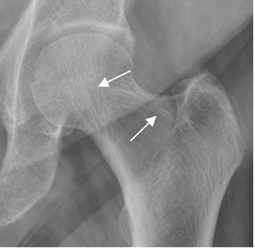

El principal hallazgo es la reducción de la densidad ósea, con disminución del número y espesor de las trabéculas del hueso esponjoso. Hay pérdida de las trabéculas transversales, con predominio de las verticales y las paralelas a los ejes de carga. (8). (Fig 35).

Fig 35. Osteoporosis.

A: Rx AP. Disminución de la densidad ósea, con prominencia de las trabéculas que siguen la orientación del eje de carga.